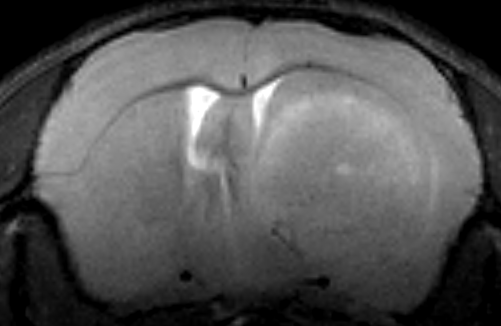

T2-gewichtete MRT-Aufnahme eines Maushirns mit Tumor

Um den Einfluss von SAMHD1 speziell im Glioblastom zu untersuchen, wurden zwei Loss-of-Function-Tumormodelle verwendet: Der Knock-out (KO) von SAMHD1 erfolgte einerseits in den Tumorzellen der betroffenen Tiere und andererseits in den tumortragenden Wirtstieren selbst. Die Implantation der Zellen erfolgte stereotaktisch im Rahmen einer „Mini-OP“ unter dem Mikroskop. Im Verlauf wurde das Tumorwachstum mittels Kleintier-MRT kontrolliert. Der zentrale Fokus des Projektes liegt auf der Analyse der vom Tumor verursachten Immunantwort.